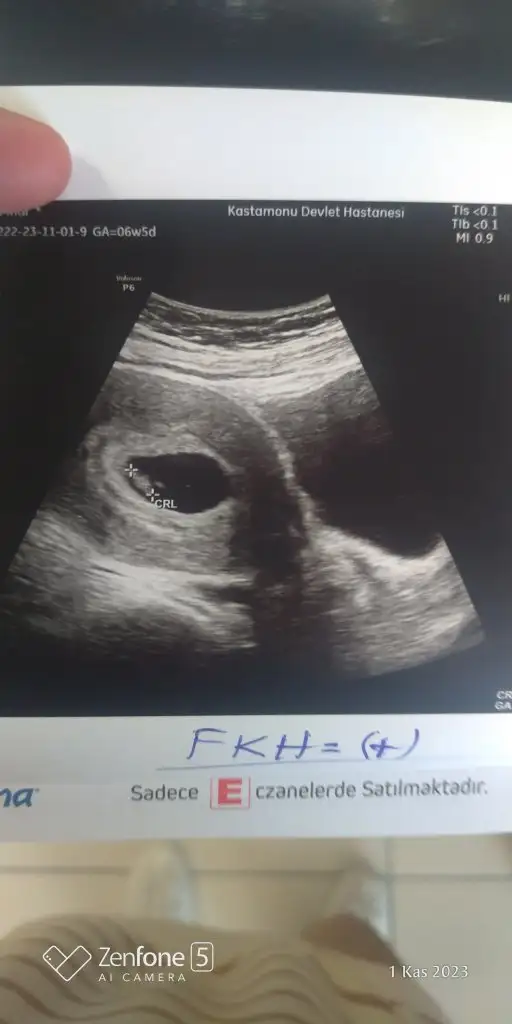

Merhaba, ben bebeğimi kaybettim.. 8 haftalıkken kalbi durdu. 9+5’te doktor muayenesine gittiğimde öğrendim. Öğrendiğimin ertesi günü de kürtaj oldum. Cinsiyetini hep çok merak ettim. Sürekli Çin, Rus, Maya takvimi vs bakıp duruyordum. En azından doğruluğu kesin olmasa bile, teoride bile olsa benim meleğim için de tahminde bulunabilir misiniz? Bu görüntü karından ultrason ve 6+4’teyken çekilmişti. Rabbim bebek bekleyen herkesin sağlıkla kucağına almasını nasip etsin.